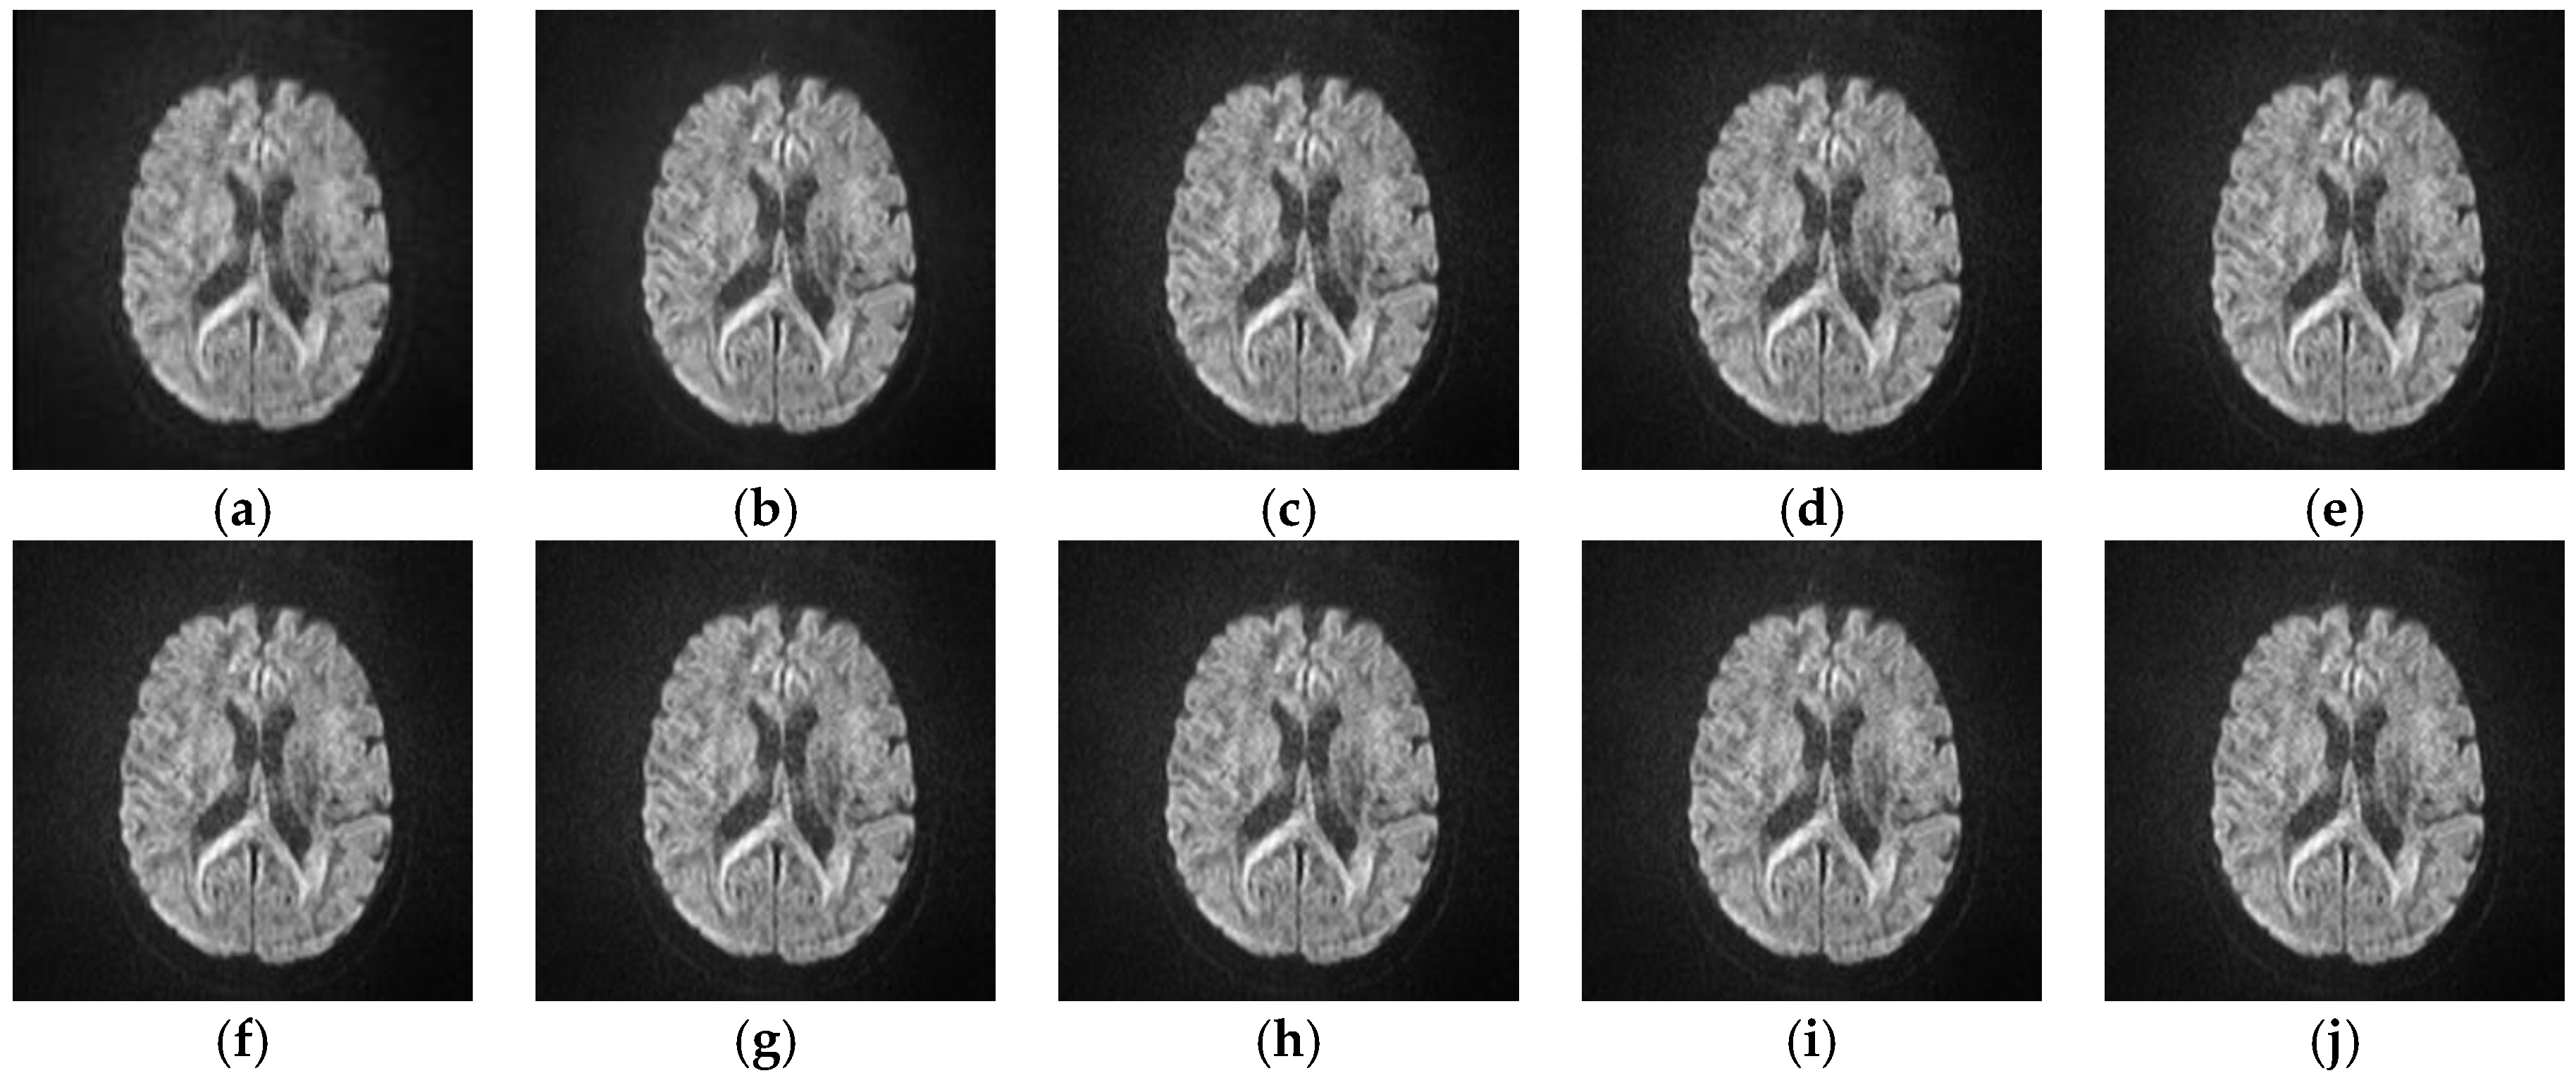

5.2.4. Analyze the Performance of Different SR Algorithms on Real Medical Images